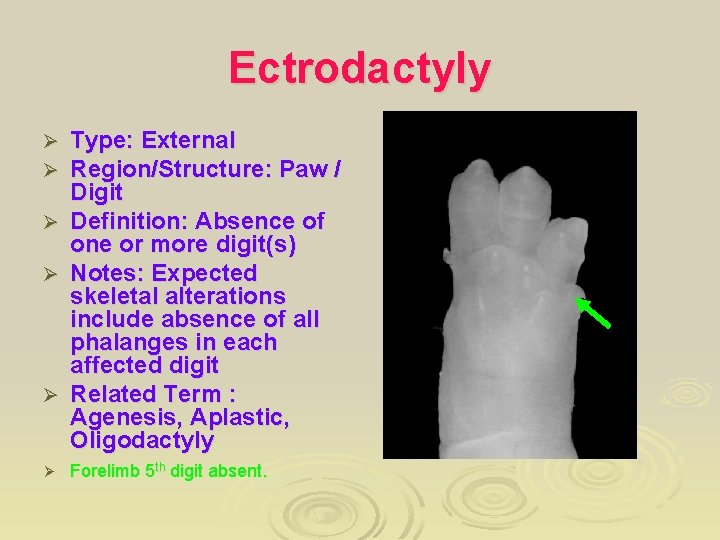

Ectrodactyly Type: External Region/Structure: Paw / Digit Ø Definition: Absence of one or more digit(s) Ø Notes: Expected skeletal alterations include absence of all phalanges in each affected digit Ø Related Term : Agenesis, Aplastic, Oligodactyly Ø Forelimb 5 th digit absent. Ø Ø